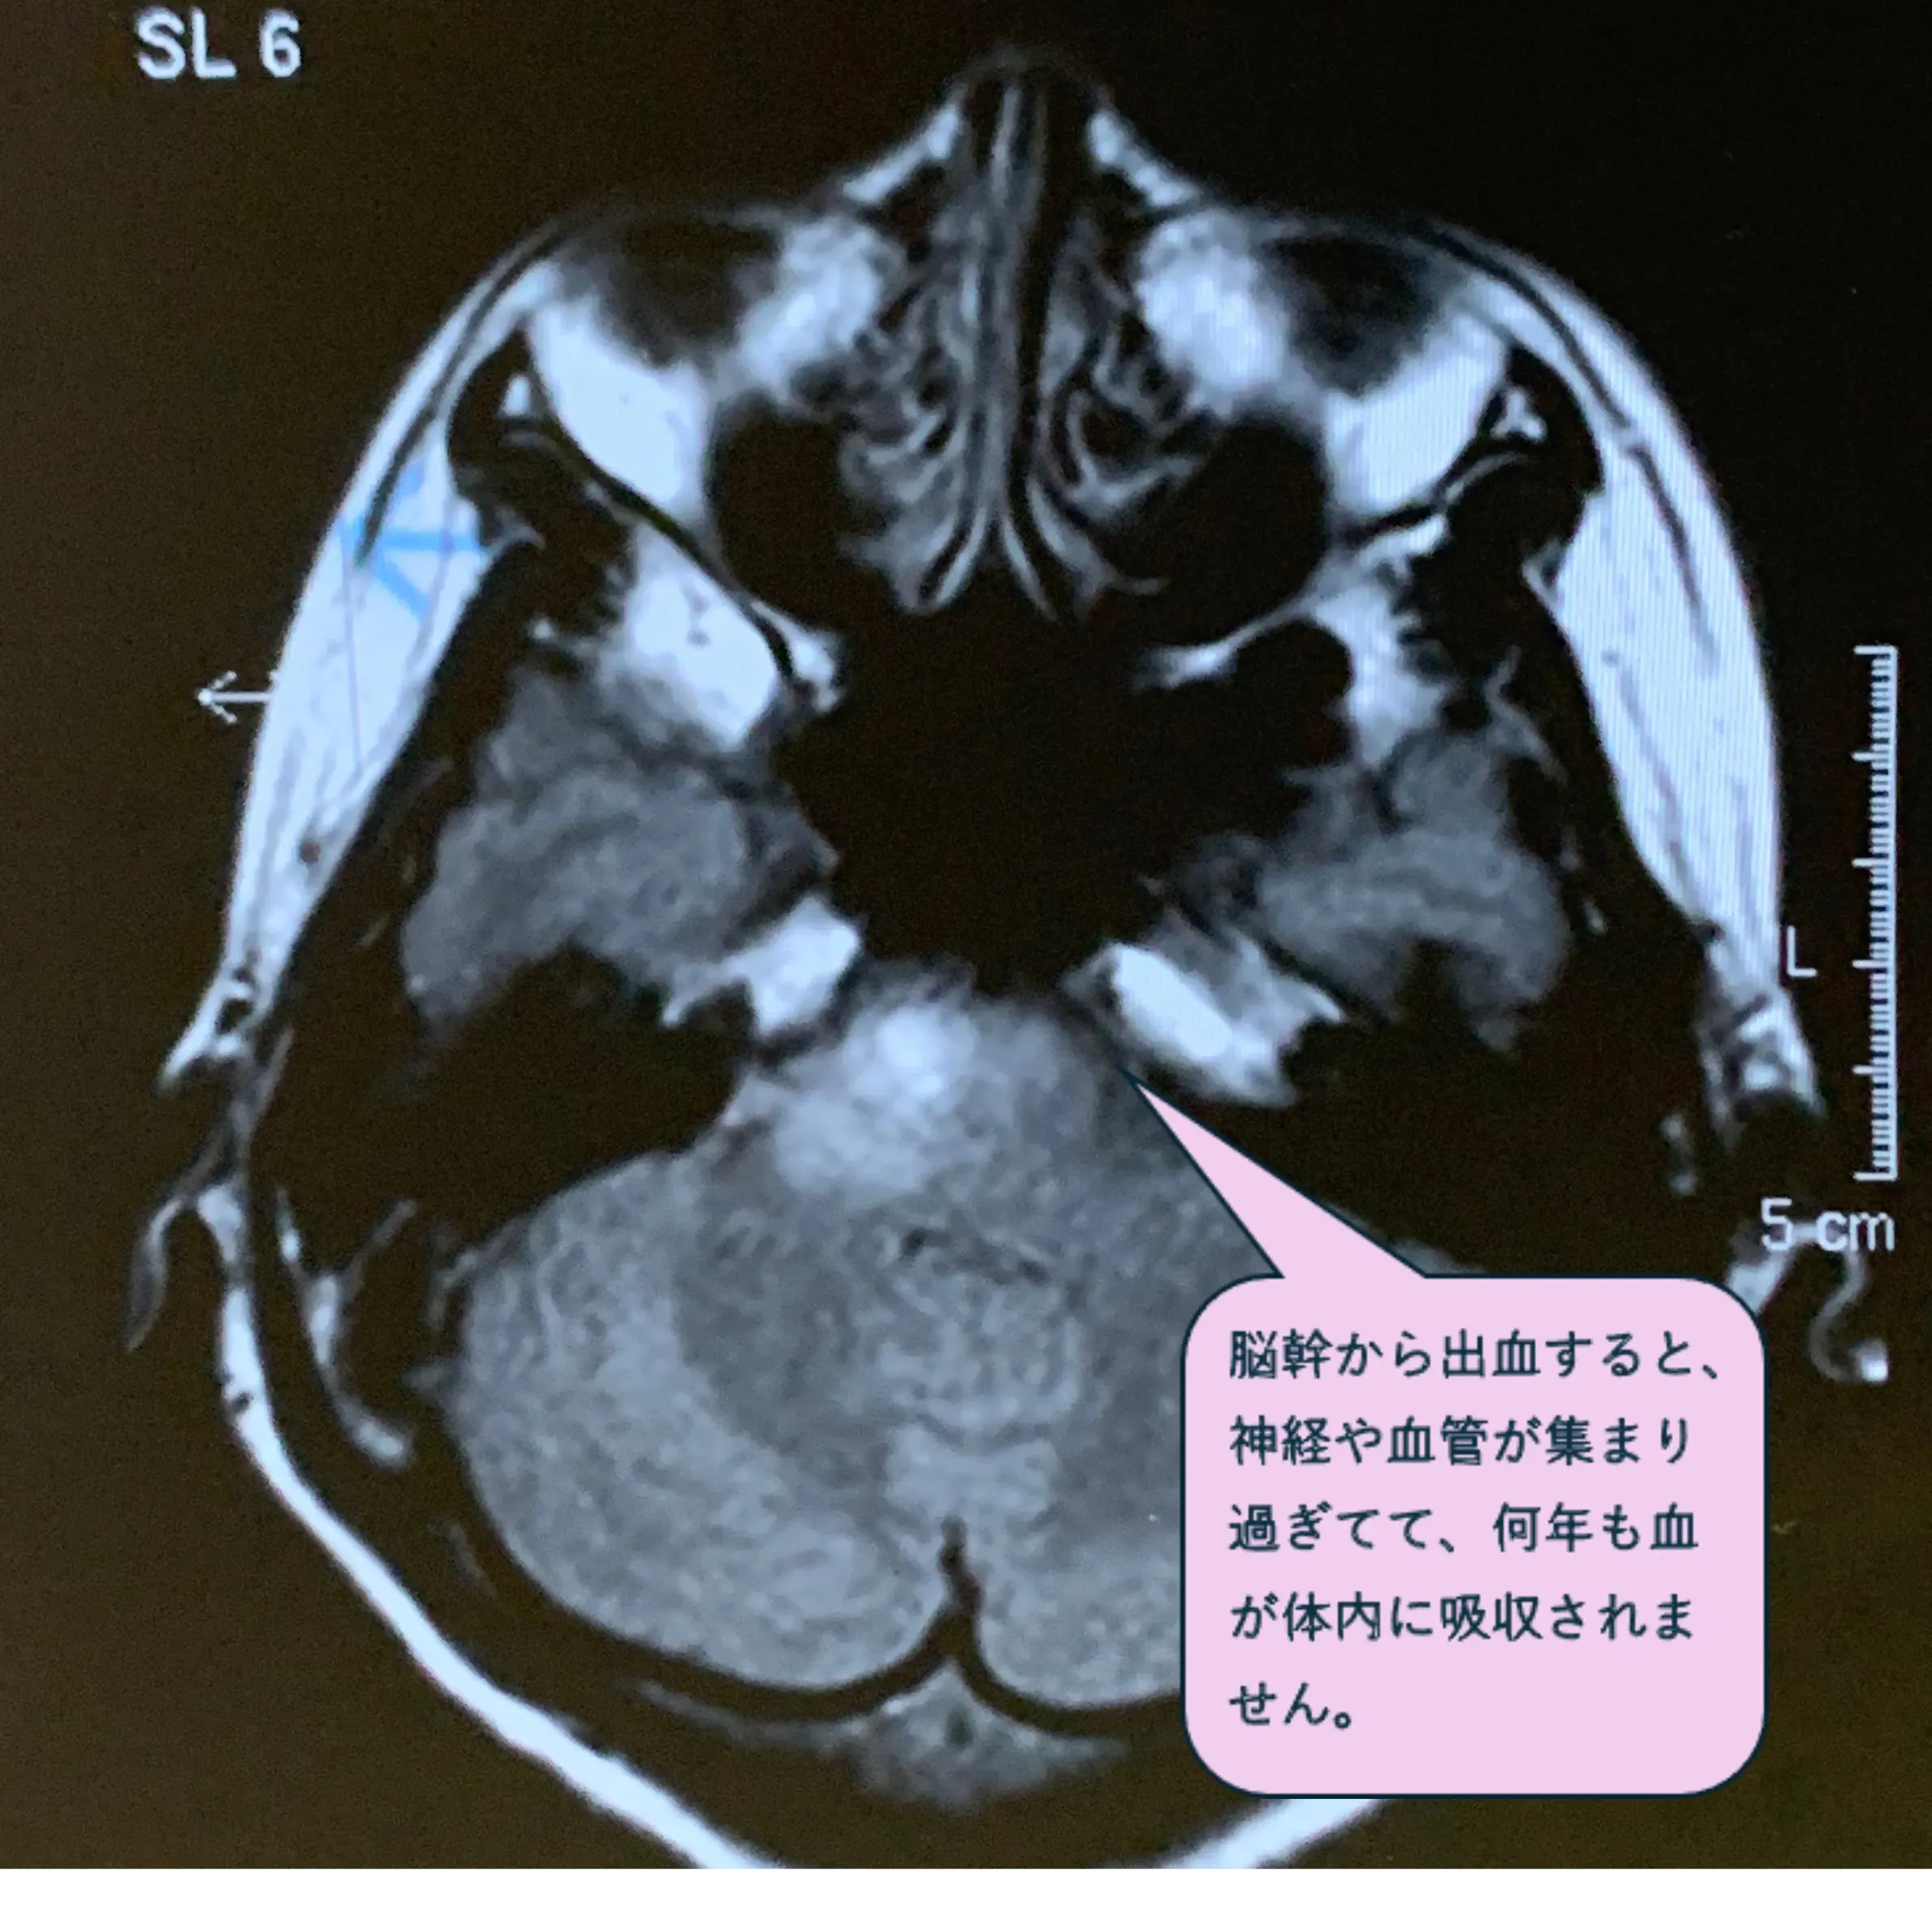

・33歳 生きる事が面白すぎて多忙を極める中、仕事中に倒れる。「脳幹出血」

後遺症なく健常に生きてます。医師も周囲もこの世の不思議だと言います。

中央左の白い影が 脳幹出血痕です。臨死体験楽しかったです。